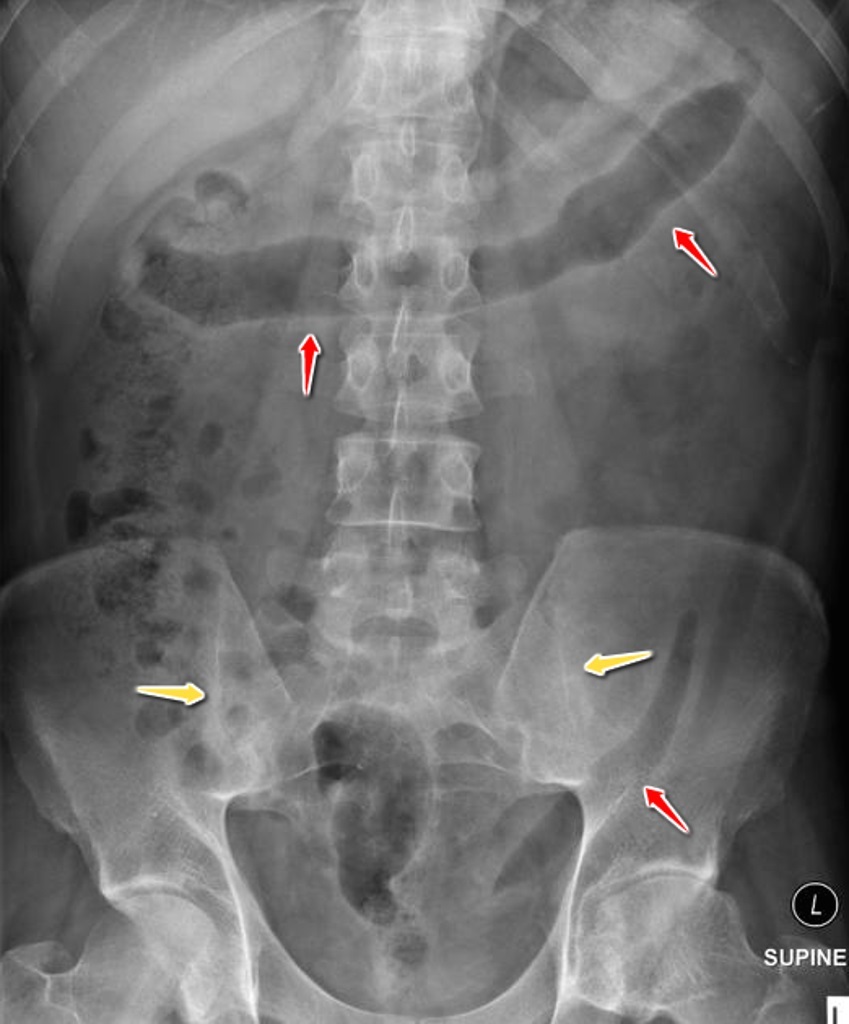

A